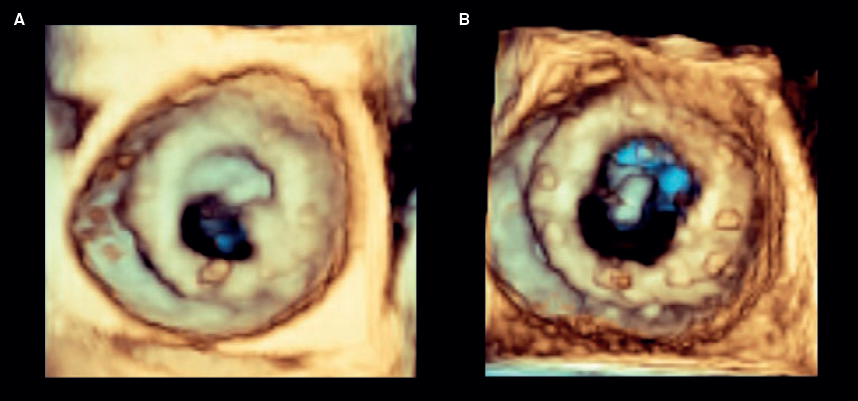

Debido a que el disco estaba bloqueado en una posición casi completamente cerrada (vídeo 1 del material adicional), optamos por un enfoque menos agresivo que el descrito por Jabbour et al.1 y en vez de manipular el disco con el catéter guía decidimos utilizar un catéter balón. Para ello, por el catéter guía se avanzó una guía de 0,014 pulgadas Balance Middleweight hacia las cavidades izquierdas. Aunque el alambre guía tendió a avanzar hacia al ventrículo izquierdo a través del espacio que dejaba el disco móvil al abrirse, después de varios intentos se pudo dirigir a través del pequeño espacio entre el disco bloqueado y el anillo protésico (figura 1) (vídeo 2 del material adicional). Con el extremo de la guía apoyado en el ápex, se avanzó suavemente un catéter balón no distensible Medtronic NC Euphora 5,0 × 15 mm que se infló varias veces a nivel del anillo mitral hasta que el disco bloqueado se liberó por completo (figura 2) (vídeos 3 y 4 del material adicional). La ecocardiografía transesofágica realizada después del procedimiento mostró la normalización de la función de la válvula protésica con un gradiente medio de 5 mmHg y un movimiento adecuado de ambos discos (figura 3). La paciente fue extubada inmediatamente después de la intervención sin complicaciones y no hubo eventos tromboembólicos ni hemorrágicos posteriores. Fue dada de alta 2 días después del procedimiento, con anticoagulantes orales y ácido acetilsalicílico. Un estudio sistemático descartó alteraciones de la coagulación y la paciente permanecía asintomática a los 12 meses de seguimiento.

Figura 3. Prótesis mitral antes (A) y después de la intervención (B). Tras la intervención percutánea se observa la apertura completa de ambos discos.